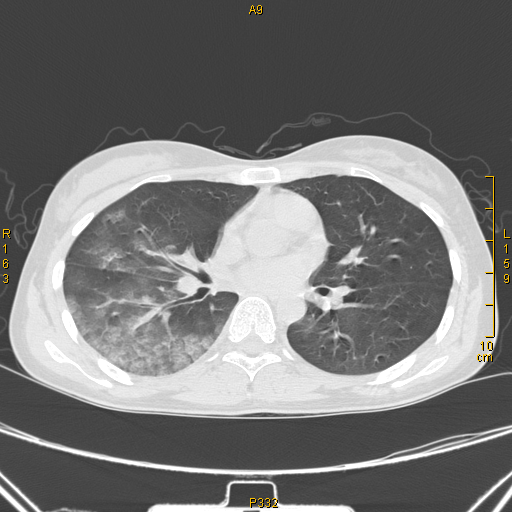

吸入性肺炎 (co中毒后误吸致右侧肺炎)